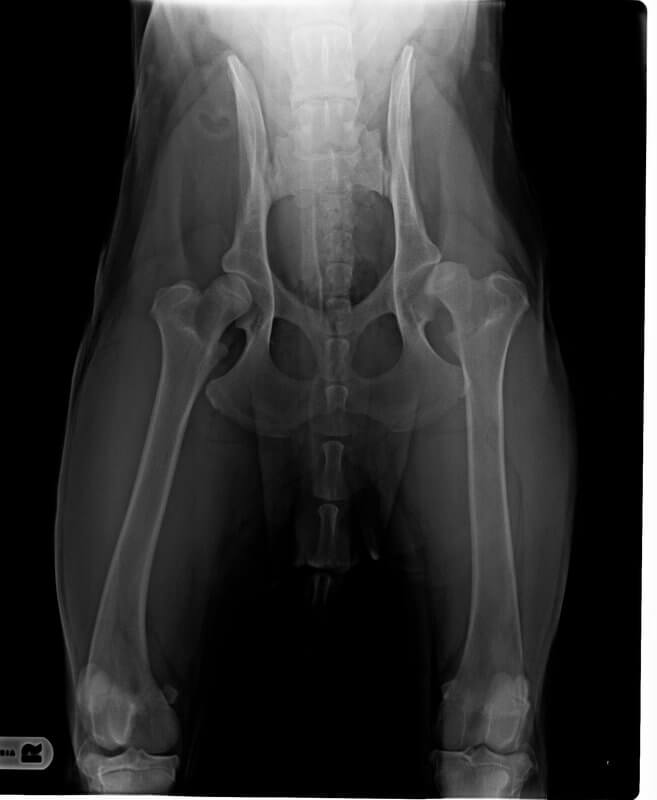

Ich kann mich da wirklich etwas hineinversetzen. Mein kleiner Großer hat auch jetzt bereits mit 10 Monaten HD, wobei (hoffentlich) nicht mit einer ganz so schlimmen Prognose.

Ruebchen nein, sieht nicht unbedingt 100%ig aus. Müssen dem jetzt entgegensteuern, mir geht es in erster Linie darum dass er keine Schmerzen hat.

Ich denke, ohne mich jetzt unbedingt auszukennen, dass wir nicht an einer OP vorbeikommen werden.

Schwere HD nach 10 Monaten ist schon ziemlich heftig.

Wenn das Humpeln bzw. "nicht belasten" wirklich "nur" auf das HD zurück zu führen sind, dann kann es nur eine schwere Hd sein bzw. kann man es definitiv nicht einfach so belassen.